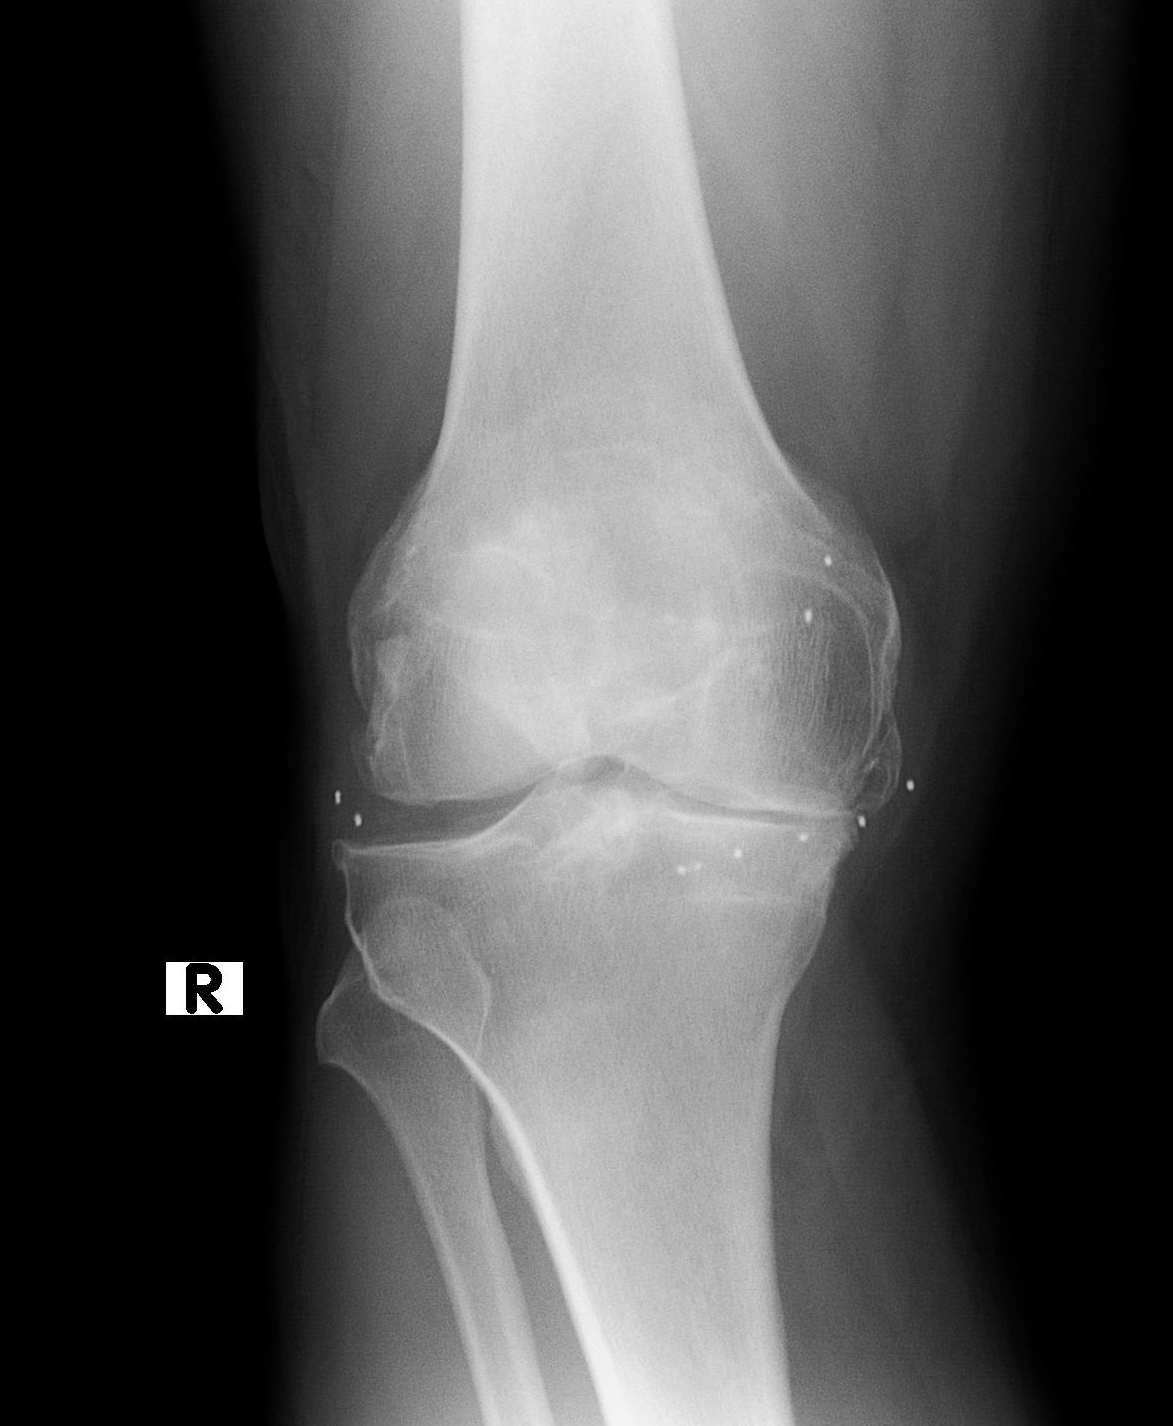

Los implantes de oro actúan a nivel de los tejidos blandos periarticulares. Los cambios funcionales y la desaparición del dolor son muy evidentes, en cambio no se observa cambio radiográfico alguno, al menos en el corto y mediano plazo. A continuación se observa un estudio de RX de un paciente con implantes de oro en ambas rodillas, con un marcado genu varo, y un cambio funcional y de mejora sintomática y de calidad de vida, inesperado incluso para el propio paciente.